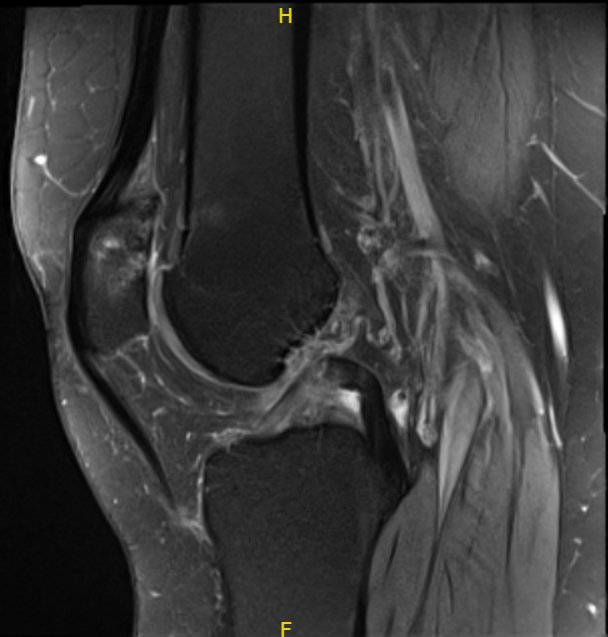

The patient presented MRI results that showed moderate to markedly advanced patellofemoral compartment chondromalacia. Free edge fraying of the medial meniscus with an obliquely oriented undersurface horizontal flap tear through the body of the medial meniscus and mild to moderate generalized medial compartment chondromalacia.

Mild free edge fraying of the lateral meniscus without a discrete tear. Trace joint effusion with an 8mm ossified loose body at the posterior aspect of the joint.

MRI-3T Left knee non-contrast